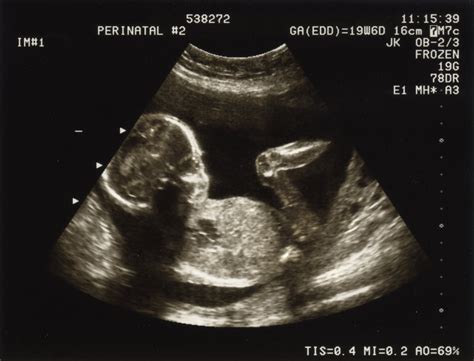

- Stergerea și dilatarea prematură a colului: La unele femei, colul uterin, deși nu este neapărat scurtat sau afectat de incompetenta cervicală, poate începe să se deschidă mai devreme. Ecografia de rutină de la mijlocul sarcinii poate releva această problemă.

- Placenta praevia: Această afecțiune, ce presupune o placentă jos inserată, în apropierea sau peste colul uterin, poate declanșa un travaliu prematur. Poate fi descoperită ecografic sau se poate manifesta prin sângerări în trimestrul II sau III de sarcină.